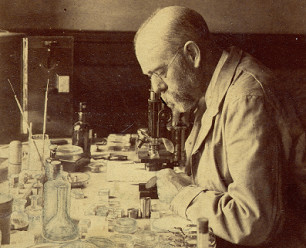

Robert Koch with a microscope in the background, in 1880 appr. [16]